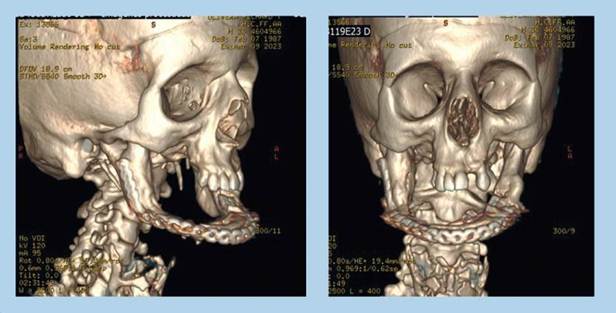

Con el archivo DICOM de la TC se realizó un biomodelo de la mandíbula para preformar la placa de reconstrucción y así disminuir los tiempos quirúrgicos.

En las figuras 6 y 7 se aprecian las imágenes postquirúrgicas de la ortopantomografía y reconstrucción tomográfica respectivamente. Se observa la placa de reconstrucción fijada con 7 tornillos.

Figura 7. Fijación de placa preformada a mandíbula.